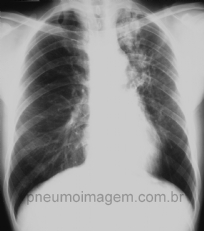

CASO CLÍNICO #19

Paciente com tosse persistente há um mês, febre e sudorese noturnas e perda do apetite. Qual o diagnóstico? Deixe seus comentários abaixo. ***** Patient with persistent cough for a month, fever and night sweats and loss of appetite. What is the diagnosis...